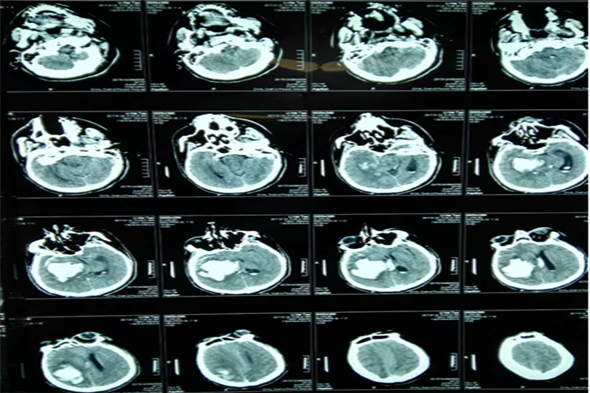

病例一 李某,男,35岁,脑出血、脑疝。

术前脑CT

术后三天脑CT

术后二周脑CT